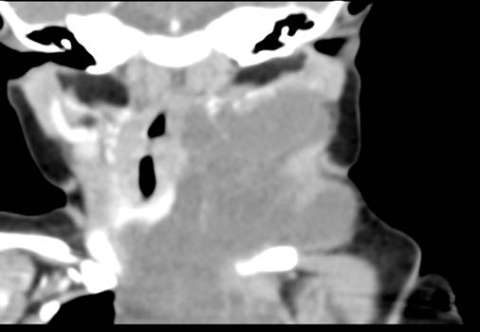

Coronal CT with contrast demonstrating large left neck macrocystic lymphatic malformation